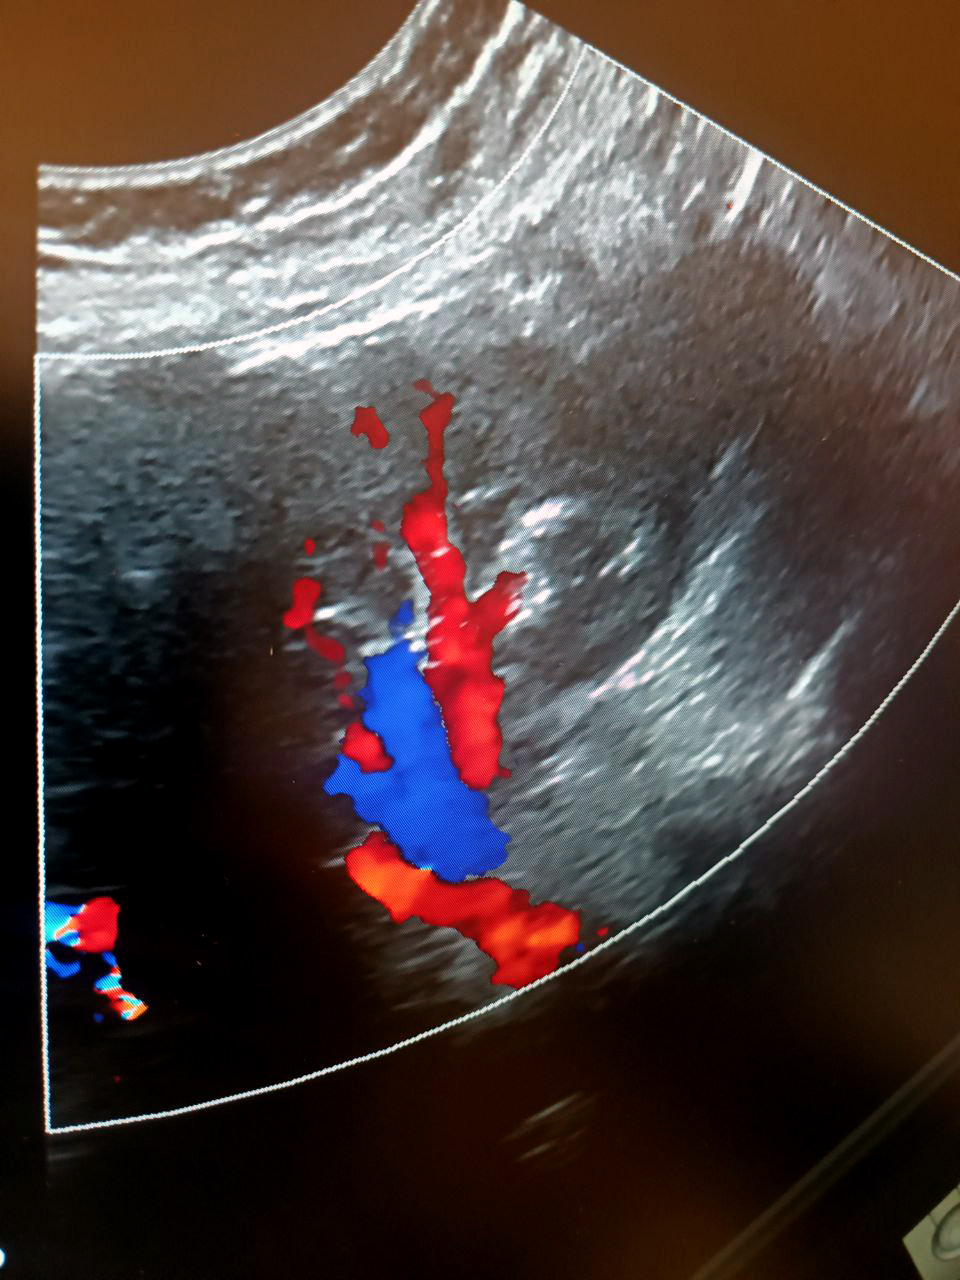

При триплексном исследовании сосудов к двум обозначенным режимам прибавляется третий — цветное доплеровское картирование (ЦДК). Черно-белая картинка на мониторе превращается в цветную, позволяя наглядно визуализировать кровоток, уловить малейшие изменения в работе сосуда, микроспазмы. Это очень важно, если мы смотрим глубокие вены или разбираемся со сложными случаями.

Визуализация сосудов почки.

При ХБП оценка кровотока в родной или трансплантированной почке показывает, насколько работоспособен орган. В первую очередь мы проверяем, нет ли дефицита кровоснабжения, а если есть, выясняем его причины — это могут быть атеросклеротические поражения, вызывающие стенозы (сужения) артерии, перегибы артерии или какие-то иные патологии. Хроническая болезнь почек сопровождается нарушениями на уровне микроциркуляции и коркового слоя, опасные изменения необходимо вовремя отследить. Пересадка почки — сложная операция. Любая операция требует динамического наблюдения, а в данном случае мы должны также оценивать, насколько хорошо приживается трансплантат. В течение первого года после пересадки пациент госпитализируется несколько раз для детального обследования, которое включает обязательную оценку параметров кровотока сосудов почечного трансплантата.